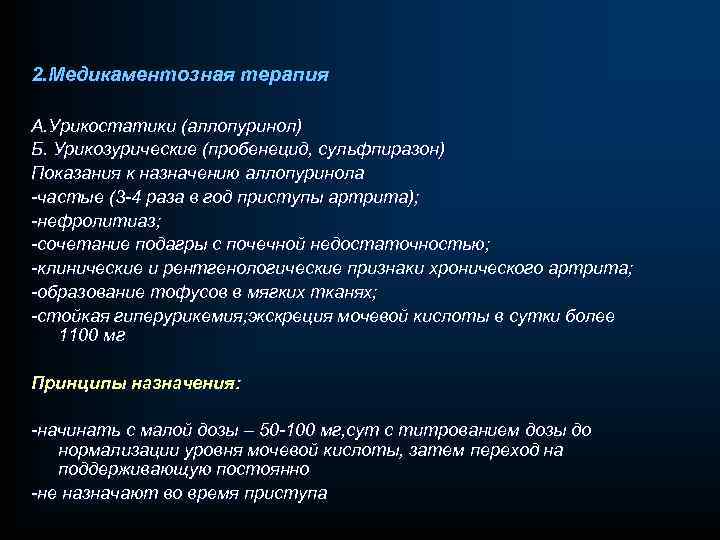

2. Медикаментозная терапия А. Урикостатики (аллопуринол) Б. Урикозурические (пробенецид, сульфпиразон) Показания к назначению аллопуринола -частые (3 -4 раза в год приступы артрита); -нефролитиаз; -сочетание подагры с почечной недостаточностью; -клинические и рентгенологические признаки хронического артрита; -образование тофусов в мягких тканях; -стойкая гиперурикемия; экскреция мочевой кислоты в сутки более 1100 мг Принципы назначения: -начинать с малой дозы – 50 -100 мг, сут с титрованием дозы до нормализации уровня мочевой кислоты, затем переход на поддерживающую постоянно -не назначают во время приступа

2. Медикаментозная терапия А. Урикостатики (аллопуринол) Б. Урикозурические (пробенецид, сульфпиразон) Показания к назначению аллопуринола -частые (3 -4 раза в год приступы артрита); -нефролитиаз; -сочетание подагры с почечной недостаточностью; -клинические и рентгенологические признаки хронического артрита; -образование тофусов в мягких тканях; -стойкая гиперурикемия; экскреция мочевой кислоты в сутки более 1100 мг Принципы назначения: -начинать с малой дозы – 50 -100 мг, сут с титрованием дозы до нормализации уровня мочевой кислоты, затем переход на поддерживающую постоянно -не назначают во время приступа